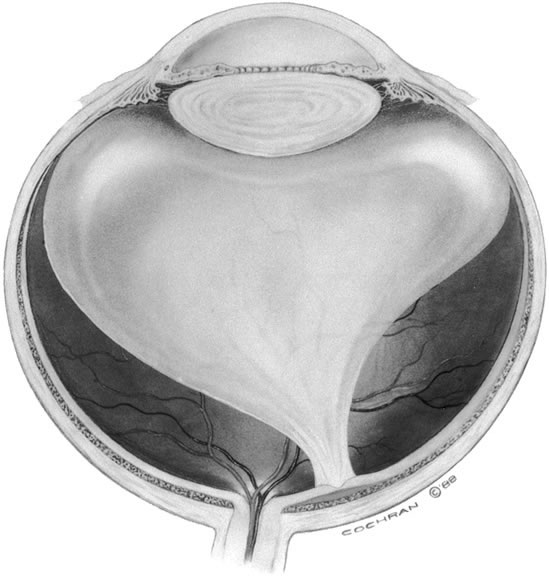

The vitreous body interfaces with a number of ocular structures through the vitreous cortex (Fig. 1). The vitreous cortex extends anteriorly from the vitreous base to form the anterior vitreous cortex and posteriorly to form the posterior vitreous cortex. Recently, the clinical importance of vitreous cortex has become increasingly apparent. The vitreous cortex has been implicated as a primary factor in a variety of vitreoretinal disorders, including retinal breaks, proliferative vitreoretinopathy (PVR), anterior hyaloidal fibrovascular proliferation, macular holes, and epiretinal membranes.

The anterior vitreous cortex or anterior hyaloid is the anterior surface layer or condensation of the vitreous body. There is no specialized membrane that constitutes the anterior vitreous cortex, but instead there is a greater density of collagen fibrils. Microscopically, the framework of collagen fibrils that run throughout the vitreous body ends in an interwoven network to form the anterior vitreous cortex. The superficial fibrils tend to run parallel to the surface in this region. The smooth surface and membrane-like appearance are due to the lamellar distribution of the cortical fibers and the associated highly polymerized mucoproteins.4,5 Anatomically, the anterior hyaloid forms the posterior limits of the posterior chamber. This portion of the vitreous cortex functions in the physiologic communication between the vitreous cavity and the aqueous humor. The anterior surface of the vitreous body separates from the pars plana approximately 1.5 mm anterior to the ora serrata. It extends medially to contact the lens posterior to the lens equator. Thus, the anterior hyaloid is in contact with the ciliary processes and the lens zonules, as well as the posterior lens capsule. The vitreous attaches to the lens capsule in a ring-like manner, forming the hyaloideocapsular ligament of Wieger. This ligament is believed by some to be synonymous with the attachment ring of the posterior zonular fibers.4 The circular area of attachment measures approximately 9 mm in diameter and is especially firm in younger persons or after intraocular inflammation.5 In this circular area the anterior hyaloid is thickened. Central to the attachment of Wieger's ligament (also known as Egger's line), the vitreous lens attachment is less pronounced and appears to be due to surface tension. This central area contains a potential space within the 9-mm ring known as Berger's space, or the patellar fossa. The anterior hyaloid then turns posteriorly to form the anterior portion of Cloquet's canal in the midportion of Berger's space. Cloquet's canal represents the remnants of the primary vitreous and can sometimes be seen with the slit lamp. It arises from the optic disc in a funnel-shaped manner, in the area of Martegiani, and extends forward to the posterior lens surface. The canal is 1 to 2 mm in width and has a down turn in the central vitreous cavity. The area of contact with the posterior lens capsule can at times be identified by a tag of embryonic tissue, known as a Mittendorf dot, located slightly nasal to the posterior pole of the lens. Similarly, a remnant of the posterior primary vitreous can occasionally be identified on the optic disc. This remnant, representing the embryonic point of exit of the hyaloid vascular system from the optic nerve head, is known as Bergmeister's papilla. The walls of Cloquet's canal are formed by a vitreous condensation rather than a true membrane (see Fig. 1).

POSTERIOR VITREOUS CORTEX

The mechanical relationship between the vitreous and the retina is mediated by the posterior vitreous cortex, which is also called the posterior hyaloid. The posterior vitreous cortex consists of relatively densely packed type II collagen fibrils arranged tangentially to the retina. The retinal basal lamina is the basement membrane of the Müller's cells that comprise the internal limiting membrane (ILM) of the retina.6,7 Ultrastructurally, the ILM consists of three layers.8 Adjacent to the end feet of the Müller's cells is the lamina rara interna. The lamina rara externa is contiguous with the vitreous cortex. In between these layers is the lamina densa. Collagen fibers of cortical vitreous are tangential to the lamina rara externa. The ILM is composed of primarily type IV collagen but also contains fibronectin, laminin, and type I collagen.9 The morphology of the ILM varies topographically in the retina. The ILM, and in particular the lamina densa, is thin in the retinal periphery and becomes increasingly thicker and irregular in the posterior retina.6,8

VITREOUS BASE

The vitreous base is a three-dimensional zone centered on the ora serrata where the vitreous is the most adherent to the retina and pars plana epithelium. It extends approximately 1.5 mm anteriorly to the ora serrata. Nasally, it extends 3.0 mm posterior to the ora and 1.8 mm posterior to the ora temporally. The functional base of the vitreous extends several millimeters into the vitreous body in this region. As the eye ages, the firm attachment of the vitreous base may extend posteriorly for several millimeters. This may lead to localized areas of enhanced vitreoretinal traction and result in retinal tears.